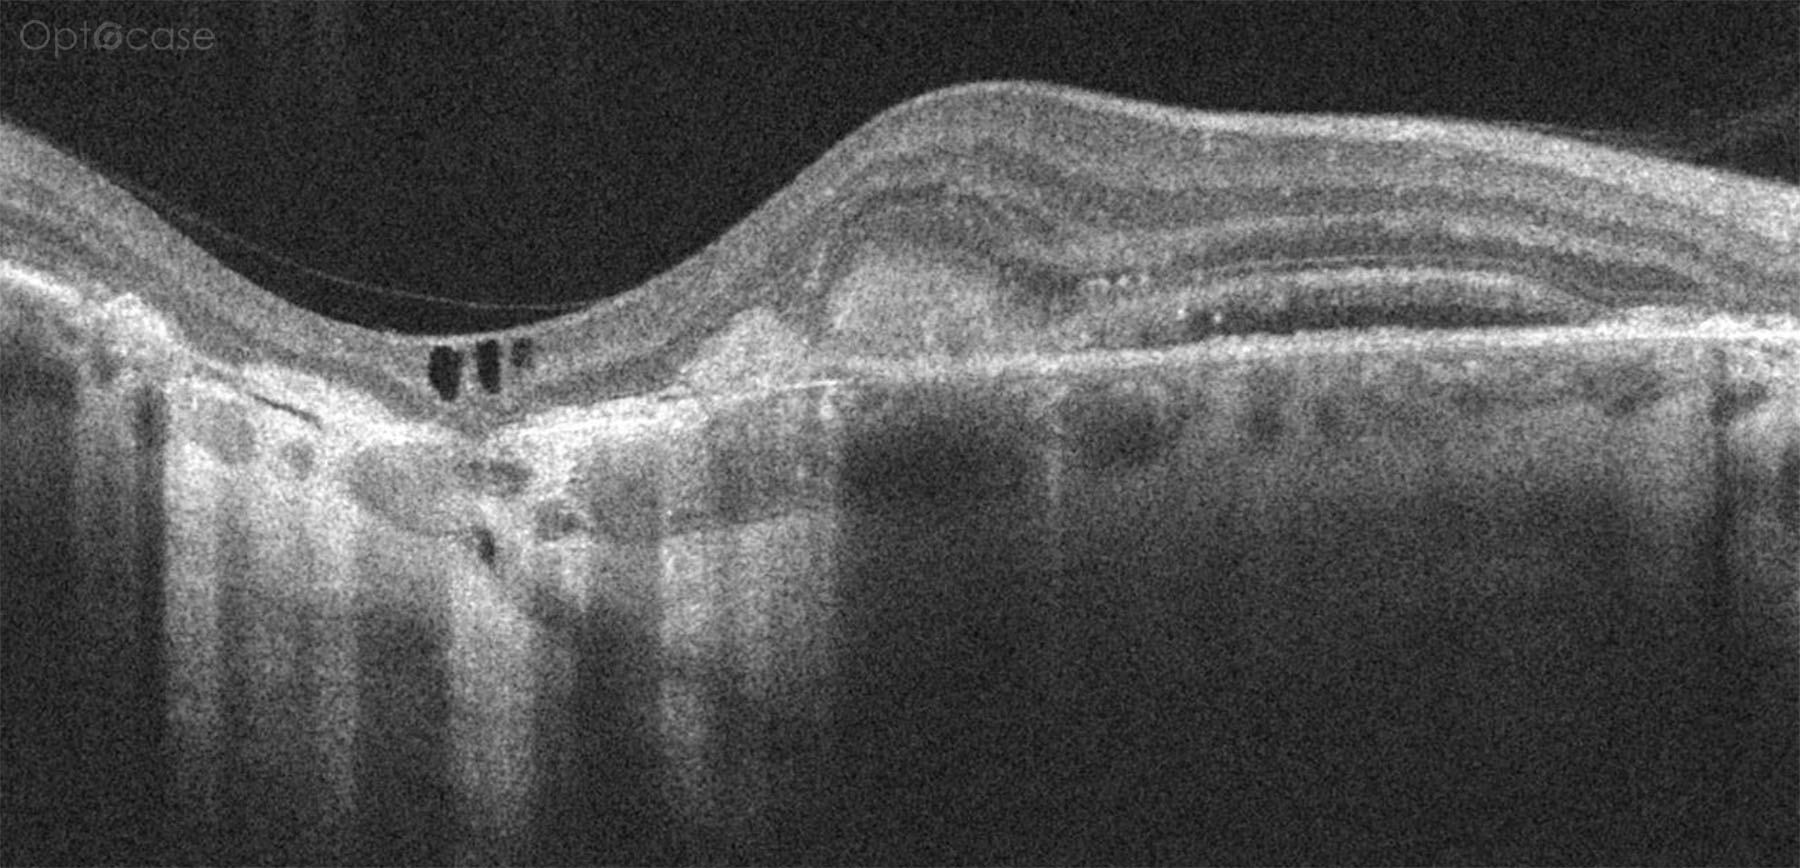

Here we can see there is significant retinal thinning to the left of the image. In the retina there are some intraretinal cysts. Below the area of retinal thinning there is excessive hyperreflectivity consistent with an area of geographic atrophy. To the right of the image (nasally) there is a small area of subretinal fluid.

This patient was diagnosed with a CNV secondary to Ocular Histoplasmosis.